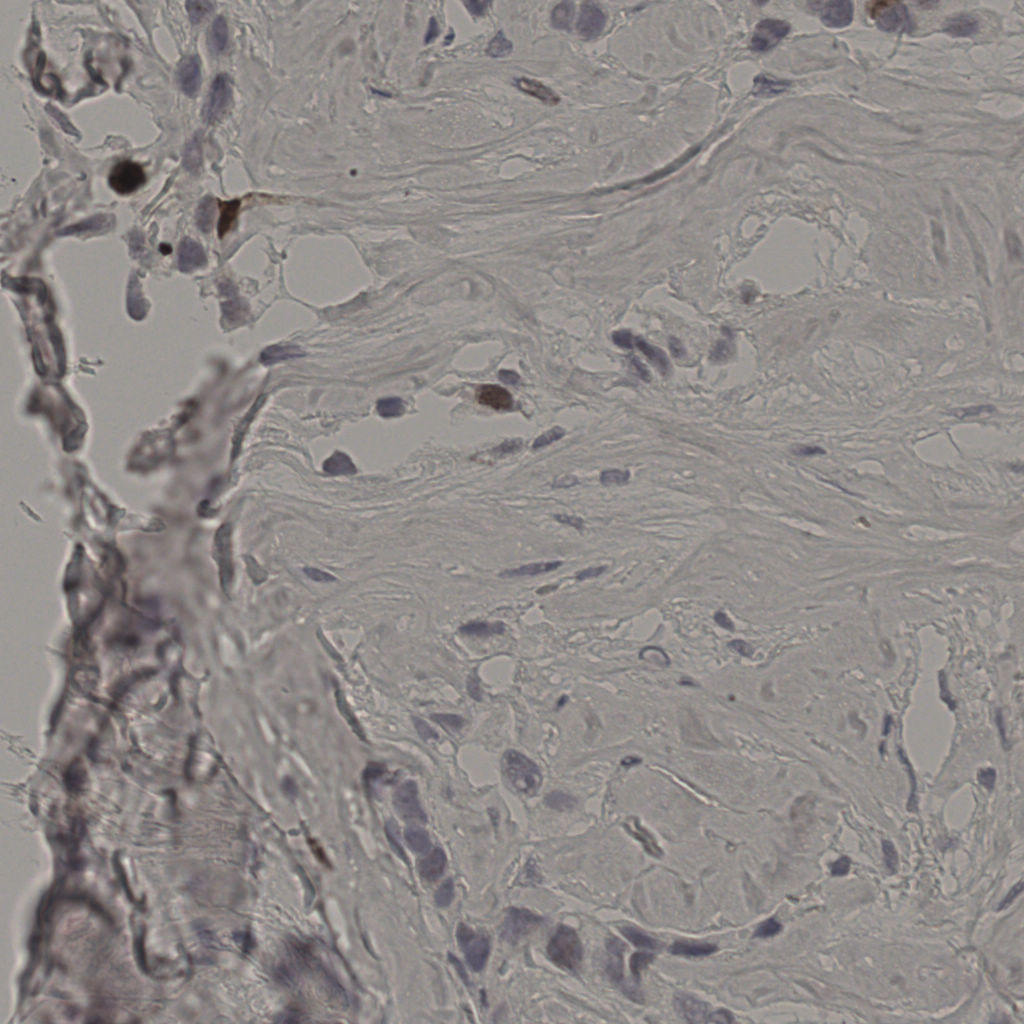

标记后

标记前